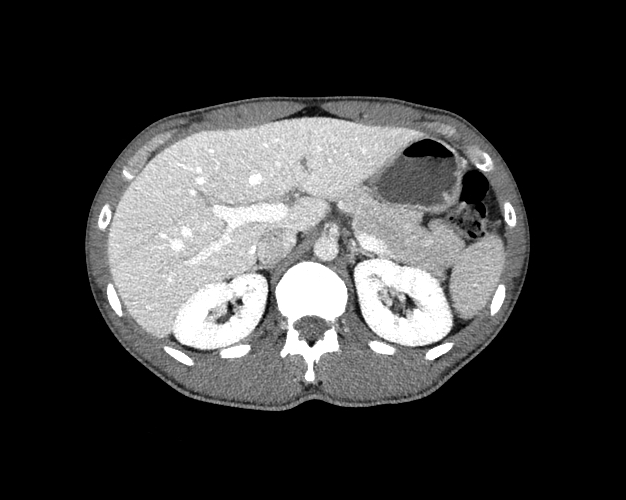

Body

Covers abdominal CT anatomy.